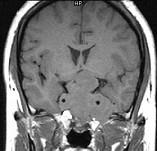

问题 女,26岁,垂体腺瘤切除术后,左眼视物模糊,请根据所提供图像,选择最可能的诊断()

选项 A.鞍区脑膜瘤 B.(垂体)复发性嫌色细胞腺瘤 C.脊索瘤 D.神经纤维瘤 E.颅咽管瘤

答案 B